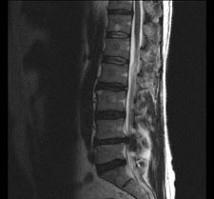

男,52岁,“坐骨神经痛”3个月余,请结合影像学检查,选出最可能的诊断 ( )A、椎间盘突出B、神经根鞘囊肿C、椎间盘炎D、硬...

相关内容:坐骨神经痛,月余,影像学,检查,选出,可能,诊断,椎间盘,神经,根鞘,囊肿